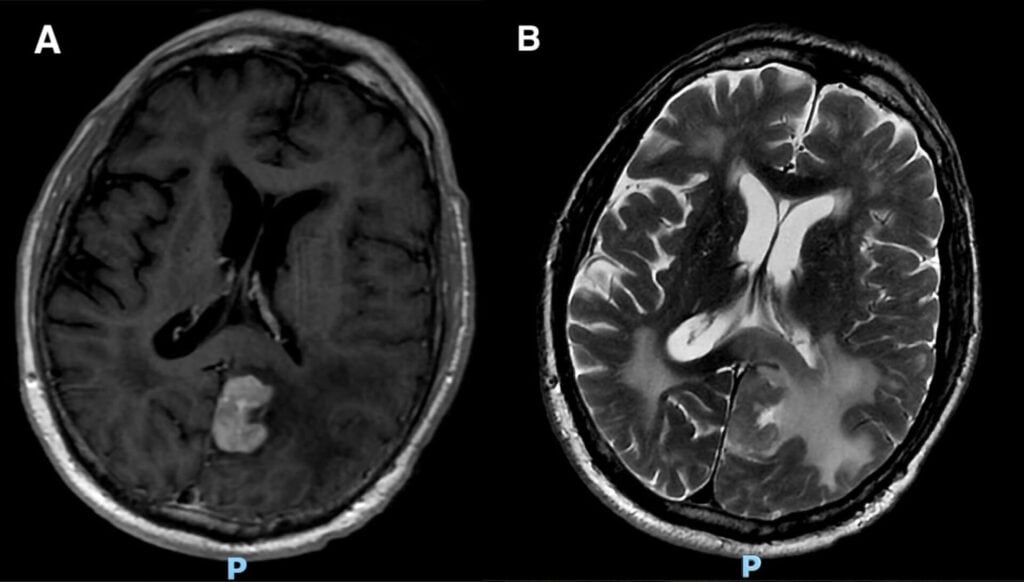

A 78-year-old male presented to the emergency department, noting difficulty with memory and simple tasks (i.e., interpreting a calendar or recalling what day/month it is) over the preceding 2-4 weeks. His past medical history was notable for prior malignant melanoma of the right shoulder s/p prior resection, squamous cell carcinoma (SCC) of the left tongue s/p resection, hypertension, hyperlipidemia, migraine, post-traumatic stress disorder, and a recent urinary tract infection. A number of laboratory studies were obtained, all of which returned normal or negative. Head CT was interpreted as normal. However, brain MRI with and without contrast demonstrated a 2.1 – 2.8 cm mass at the level of the left parieto-occipital lobe with significant surrounding edema (Figure 1).

Figure 1. Brain MRI axial T1 post-contrast sequence (A) and axial T2 propeller (B) demonstrating left parieto-occipital lobe lesion with surrounding vasogenic edema.

Consults to neurology, oncology, neurosurgery, and optometry were placed. A tentative differential for the lesion was entertained with concern for possible intracranial metastasis (stemming from prior cancers), primary central nervous system (CNS) neoplasm, or CNS lymphoma. The primary concern initially was that the lesion likely represented intracranial metastasis from the patient’s past melanoma. The patient was initiated on oral dexamethasone 4 mg BID in an effort to mitigate the impact of the lesion’s surrounding edema on nearby brain structures. After discussing various management options, the decision was ultimately made for neurosurgery to perform stereotactic brain biopsy. The patient’s brain biopsy returned with findings consistent with high-grade B-cell lymphoma.